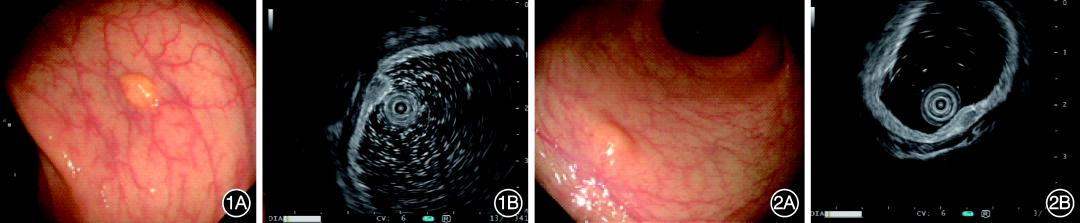

49例确诊R‑NENs病例中,48例(97.96%)结肠镜下表现为广基黏膜下隆起,表面光滑,淡黄或白色;1例表现为息肉样隆起,表面水肿。MEUS提示17例起源于第2层,即黏膜深层,见图1;32例起源于第3层,即黏膜下层,见图2。黏膜深层起源组与黏膜下层起源组比较,2组在肿瘤长径、超声内镜下回声强度、回声均匀度和病理分级构成方面差异均无统计学意义,2组在肿瘤距肛门距离构成方面差异有统计学意义,见表1。黏膜深层起源组肿瘤距肛门距离以>5~10 cm为主[64.71%(11/17)],距离≤5 cm仅占17.65%(3/17);黏膜下层起源组肿瘤距肛门距离虽也以>5~10 cm为主[53.12%(17/32)],但占比较黏膜深层起源组有所下降,同时距离≤5 cm占比较黏膜深层起源组有大幅上升[43.75%(14/32)]。

图1 黏膜深层起源的直肠神经内分泌肿瘤 1A:结肠镜下表现;1B:小探头超声内镜下表现 图2 黏膜下层起源的直肠神经内分泌肿瘤 2A:结肠镜下表现;2B:小探头超声内镜下表现